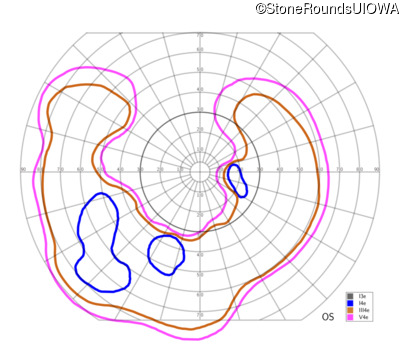

This 47 year old woman was born with a supernumerary digit on the ulnar side of both hands. As a young child, her best corrected visual acuity was completely normal. She had no difficulties with her vision until age 30 when her visual acuity could no longer be corrected to 20/20 and she began to notice some night blindness.

The clinical features supporting the diagnosis of Bardet Biedl syndrome in this patient include: bone-spicule-like pigmentation, narrowed arterioles and macular atrophy on ophthalmoscopy; photoreceptor loss on OCT; ulnar polydactyly, obesity, abnormal cognition, hypertension; and, normally sighted parents.